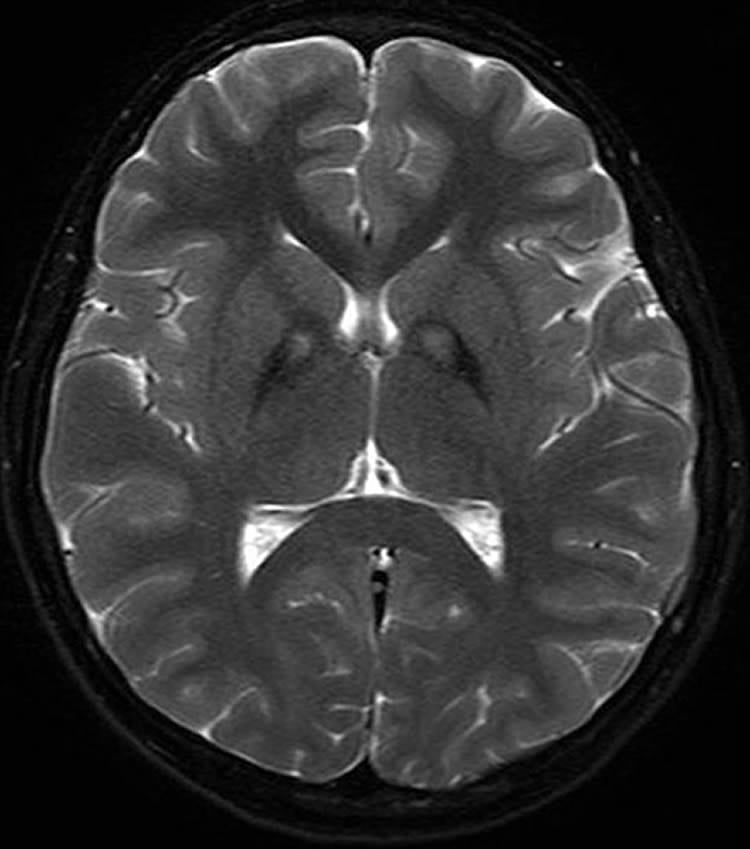

Conventional MRI cannot detect early signs of Parkinson’s, so the Oxford researchers used an MRI technique, called resting-state fMRI, in which people are simply required to stay still in the scanner. They used the MRI data to look at the ‘connectivity’, or strength of brain networks, in the basal ganglia – part of the brain known to be involved in Parkinson’s disease.

The team compared 19 people with early-stage Parkinson’s disease while not on medication with 19 healthy people, matched for age and gender. They found that the Parkinson’s patients had much lower connectivity in the basal ganglia.